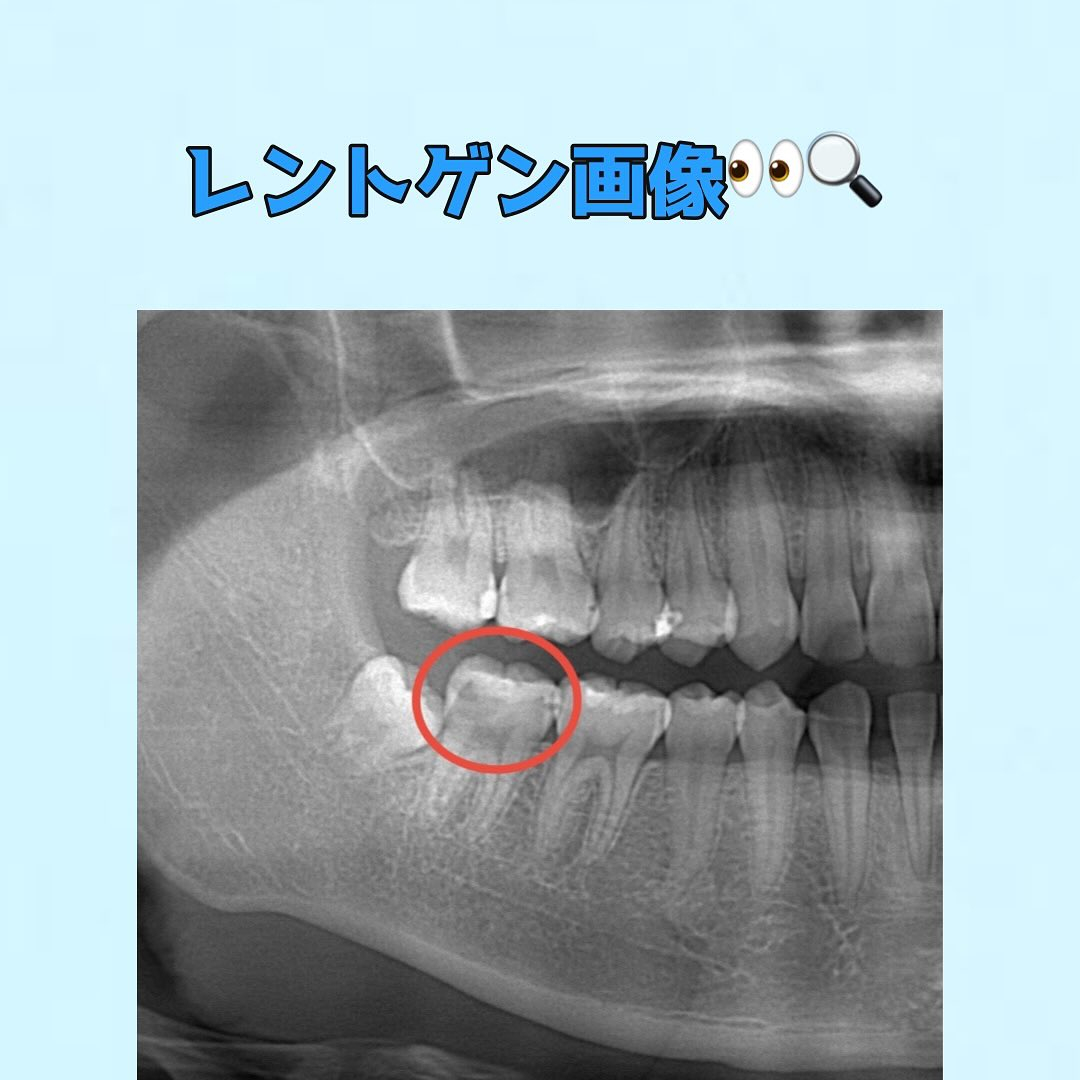

レントゲンの画像では

→赤〇で囲んだ部分が黒く影になっているのが分かります✍️

これが虫歯の所見なのです👀

歯科にはレントゲンが2つあり、今回の様な口全体が写るレントゲンをパノラマレントゲンと言います✍️

初診時に撮影する事が多いのですが、全体の歯の本数や顎関節の状態、虫歯の状態を大まかに把握することが出来ます💪

この方は、虫歯が神経にほぼ触れている事が分かった為神経を取る処置からスタートし、その隣の親知らずも今後抜歯する予定です☝️